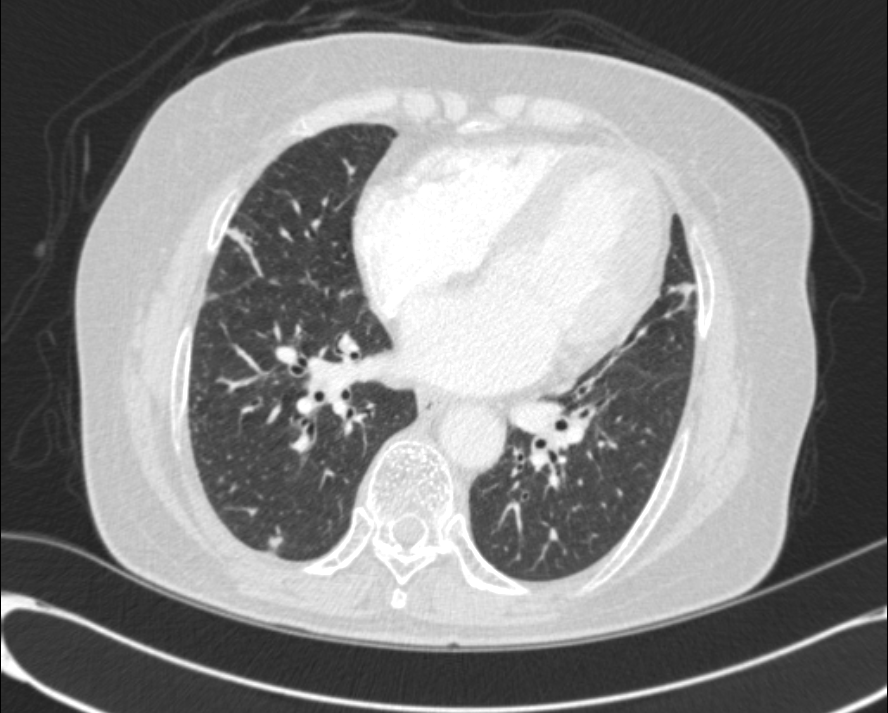

DOE  ÁּҷΠ evaluation  À§ÇØ ÃÔ¿µÇÑ  CXR ¹× chest CT ¼Ò°ßÀÔ´Ï´Ù.

* CXR °ú  chest CT  »çÁøÀÔ´Ï´Ù.

¶Ñ·ÇÇÑ ¿µ»óÀ» À§ÇØ f/u Áß¿¡ ÂïÀº »çÁøÀ» ÷ºÎÇÏ¿´½À´Ï´Ù.

l  Chest CT

Progression of multiple small nodules in both lungs, along peri-BV and ILS, dominant on RUL and RML. No significant change of several small LNs in both hilar and mediastinum.   COPD: diffuse bronchitis. LH enlarge and PAH.